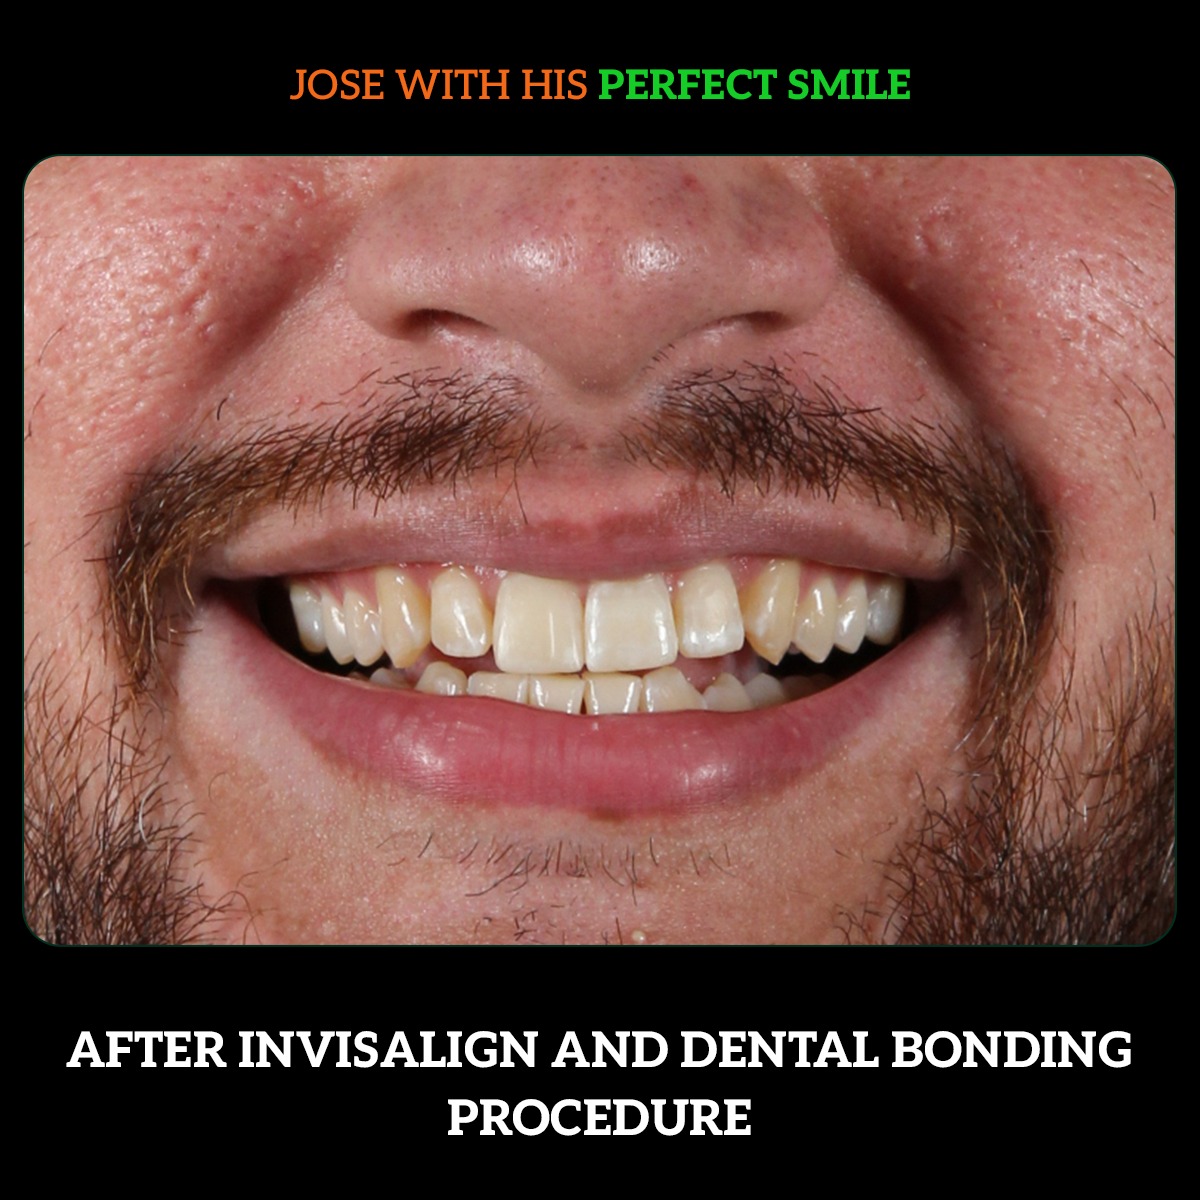

Jose Alacanter Invisalign bonding Transformation

patient concern: gaps and discoloration on front tooth